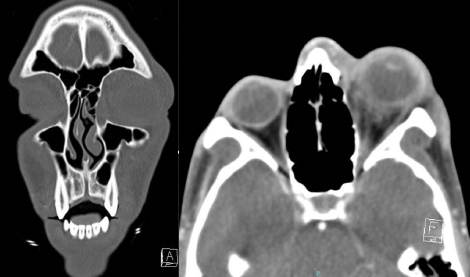

Diagnostic Imaging

First-line diagnostic imaging is Computed Tomography (CT) of the Orbit and Maxillofacial region in thin cuts. Contrast is necessary if an abscess is suspected. Magnetic Resonance Imaging (MRI) of the Orbit is typically second-line unless there is a high suspicion of a progressive orbital sign without a source. MRI offers high resolution of soft tissue in the orbit and periorbital region. This allows improved visualization of an orbital or scleral abscess, cavernous thrombosis, meningeal involvement, or cranial involvement. [11]

Computed Tomography (CT) of the Orbit and Maxillofacial Region

- Most often the primary imaging modality for panophthalmitis.

- Orbital cuts (1mm slices) allow the highest resolution of the orbit and periorbital region.

- Excellent for spatial resolution, trauma, and bony tumors.

- Contrast enhances visualization of high vascular lesions or lesions with abnormal vascular permeability.

- No contrast is adequate to assess for orbital cellulitis components for fat stranding.

- Contrast is recommended to assess for abscess (subperiosteal).